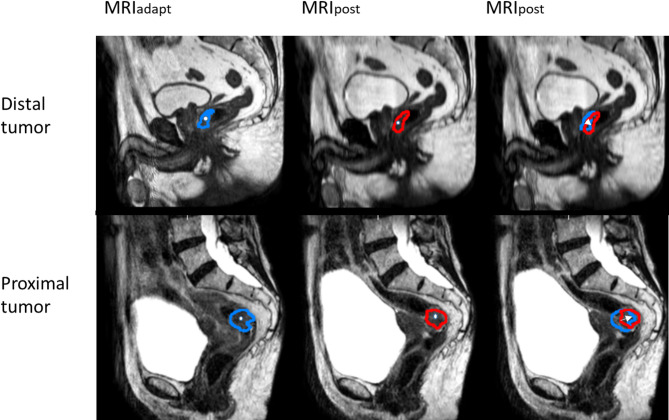

Methods: Seventy-seven rectal cancer patients, treated with short course radiotherapy (SCRT) on a 1.5T MR-Linac, were included in the study. For all five treatment fractions per patient, the GTV of the primary tumor was manually delineated on T2-weighted images acquired for online plan adaptation (MRIadapt). GTV delineations on the MRI acquired for verification after irradiation (MRIpost) were obtained by patient-specific fine-tuning of a population-based GTV autosegmentation model using the delineation on MRIadapt. The intrafraction motion was calculated as ¾ of the center of gravity (COG) displacement of the GTV between MRIadapt and MRIpost. PTV margins were calculated using the Van Herk recipe. The effect of tumor volume, circumference and location in the rectum on intrafraction motion was studied using linear mixed effect modeling and individualized margins were calculated for each group.

Results: Intrafraction motion was correlated with tumor location with larger displacement in Anterior-Posterior (p = 0.001) and Cranial-Caudal (CC; p = 0.043) direction for caudal tumors compared to proximal tumors (lower border starting > 5 cm from anorectal junction). For tumor volume, a significant (p = 0.049), but small association with Left-Right motion was found, with larger tumors exhibiting larger motion. PTV margins required for the full cohort were 2.8 mm LR, 6.3 mm AP, 2.2 mm cranial and 5.6 mm caudal. Individualizing on tumor location resulted in AP margin of 3.5 mm for proximal rectal tumors and 6.7 mm for distal rectal tumors. Margins in CC direction were 3.2 mm for proximal rectal tumors and asymmetrically 2.0 mm cranial and 6.0 mm caudal for distal rectal tumors.